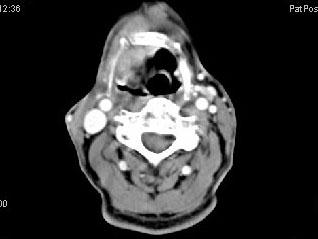

问题 男,63岁,咽喉部不适约一年,近2个月经常咳嗽,痰中带有血丝,CT如图所示,应诊断为 ( )

选项 A、声门上型喉癌 B、混合型喉癌 C、声门型喉癌 D、声门下型喉癌 E、梨状窝癌

答案 A